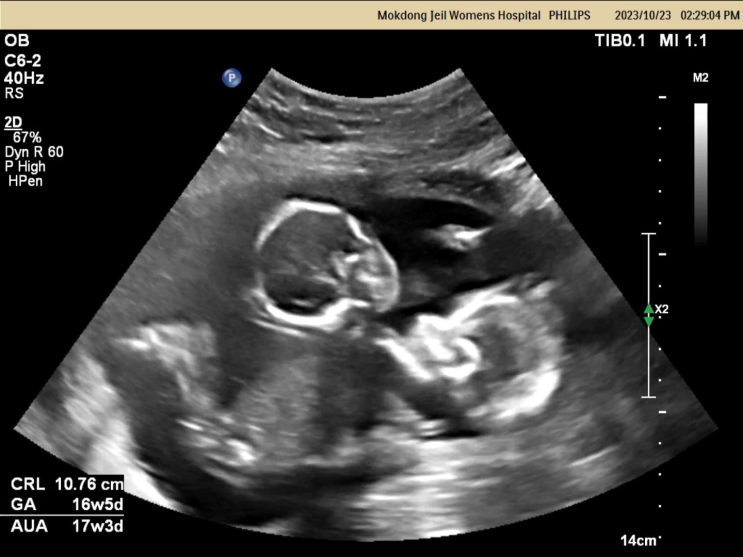

[임신일기] 임신 17-19차 일상기록 / 난임병원 졸업 / 양수검사 결과발표

10.16(월) 지구에 온 지 17주 양수검사를 하니 오히려 편해진 마음 몸 상태는 생각보다 편안해서 즐겁게 임...

[임신일기] 임신16주차 압구정 함춘 양수검사 비용 후기 / 서비스, 친절은 평범한 산부인과

10.9(월) 임신 16주차, 이제 5개월 알콩이 달콩이가 지구별에 오기 까지 D-168일 빨리 만나고 싶어 우리 ...